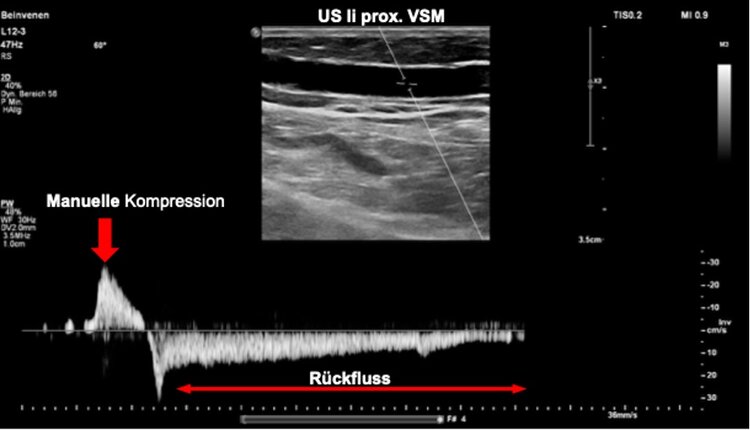

Die Diagnose erfolgt zum einen klinisch (sichtbare Varizen (Ab bildung 1b), typische «Venenzeichen» und Wunden) bzw. symptomatisch (Schwere, Schwellungen der Beine), zum anderen apparativ mittels Duplexsonographie (Abbildung 2) und/oder Venenfunktionsmessungen.